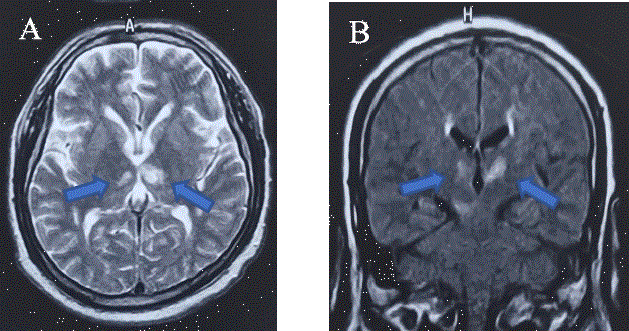

Likewise, the protocol for cerebral infarction was performed and the following results were obtained in laboratory studies: normal blood chemistry, lipid profile and thyroid profile; imaging studies: electrocardiogram and transthoracic and transesophageal echocardiogram without alterations; carotid ultrasound with evidence of atherothrombotic plaque with bilateral involvement of 40% right and 70% left (not being a candidate, by assessment of interventional neurology and radiology, for prosthesis); simple cranial tomography at 12 and 48 hours without data of hemorrhage or early data of ischemia. Simple magnetic resonance imaging of the brain was also performed (Figure 1), which showed bilateral thalamic hyperintensity in Fluid-Attenuated-Inversion-Recovery (FLAIR) with diffusion restriction in Diffusion Weighted Imaging (DWI), and Percheron syndrome was integrated due to the involvement of the bilateral territory corresponding to the paramedian artery derived from the proximal P1 segment of the posterior cerebral artery.

Figure 1 A) Axial T2 FLAIR MRI showing bilateral ischemic infarction in the thalamic region without evidence of white matter lesions, and without evidence of hemorrhage or infarct complications (blue arrows). B) DWI is observed with diffusion restriction and with lesions present in bilateral thalamic region (blue arrows), in a coronal section without presence of infarct complications, without hemorrhage or midline displacement.